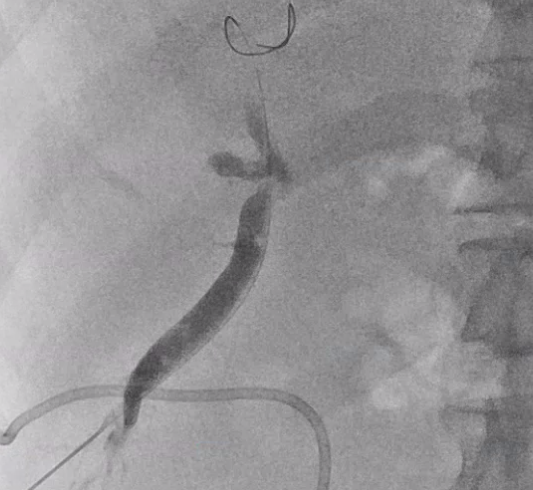

간내담관 천자에 성공했다면 반 이상은 끝난 겁니다

바늘을 통해 와이어를 넣고, 와이어를 따라서 배액관이 들어갑니다.

배액관은 지난 글에서 알려드렸던

이런 돼지 꼬리 모양의 카테터를 넣어 배액관이 잘 빠지지 않게끔 해줍니다. (이름도 돼지 꼬리 입니다.)